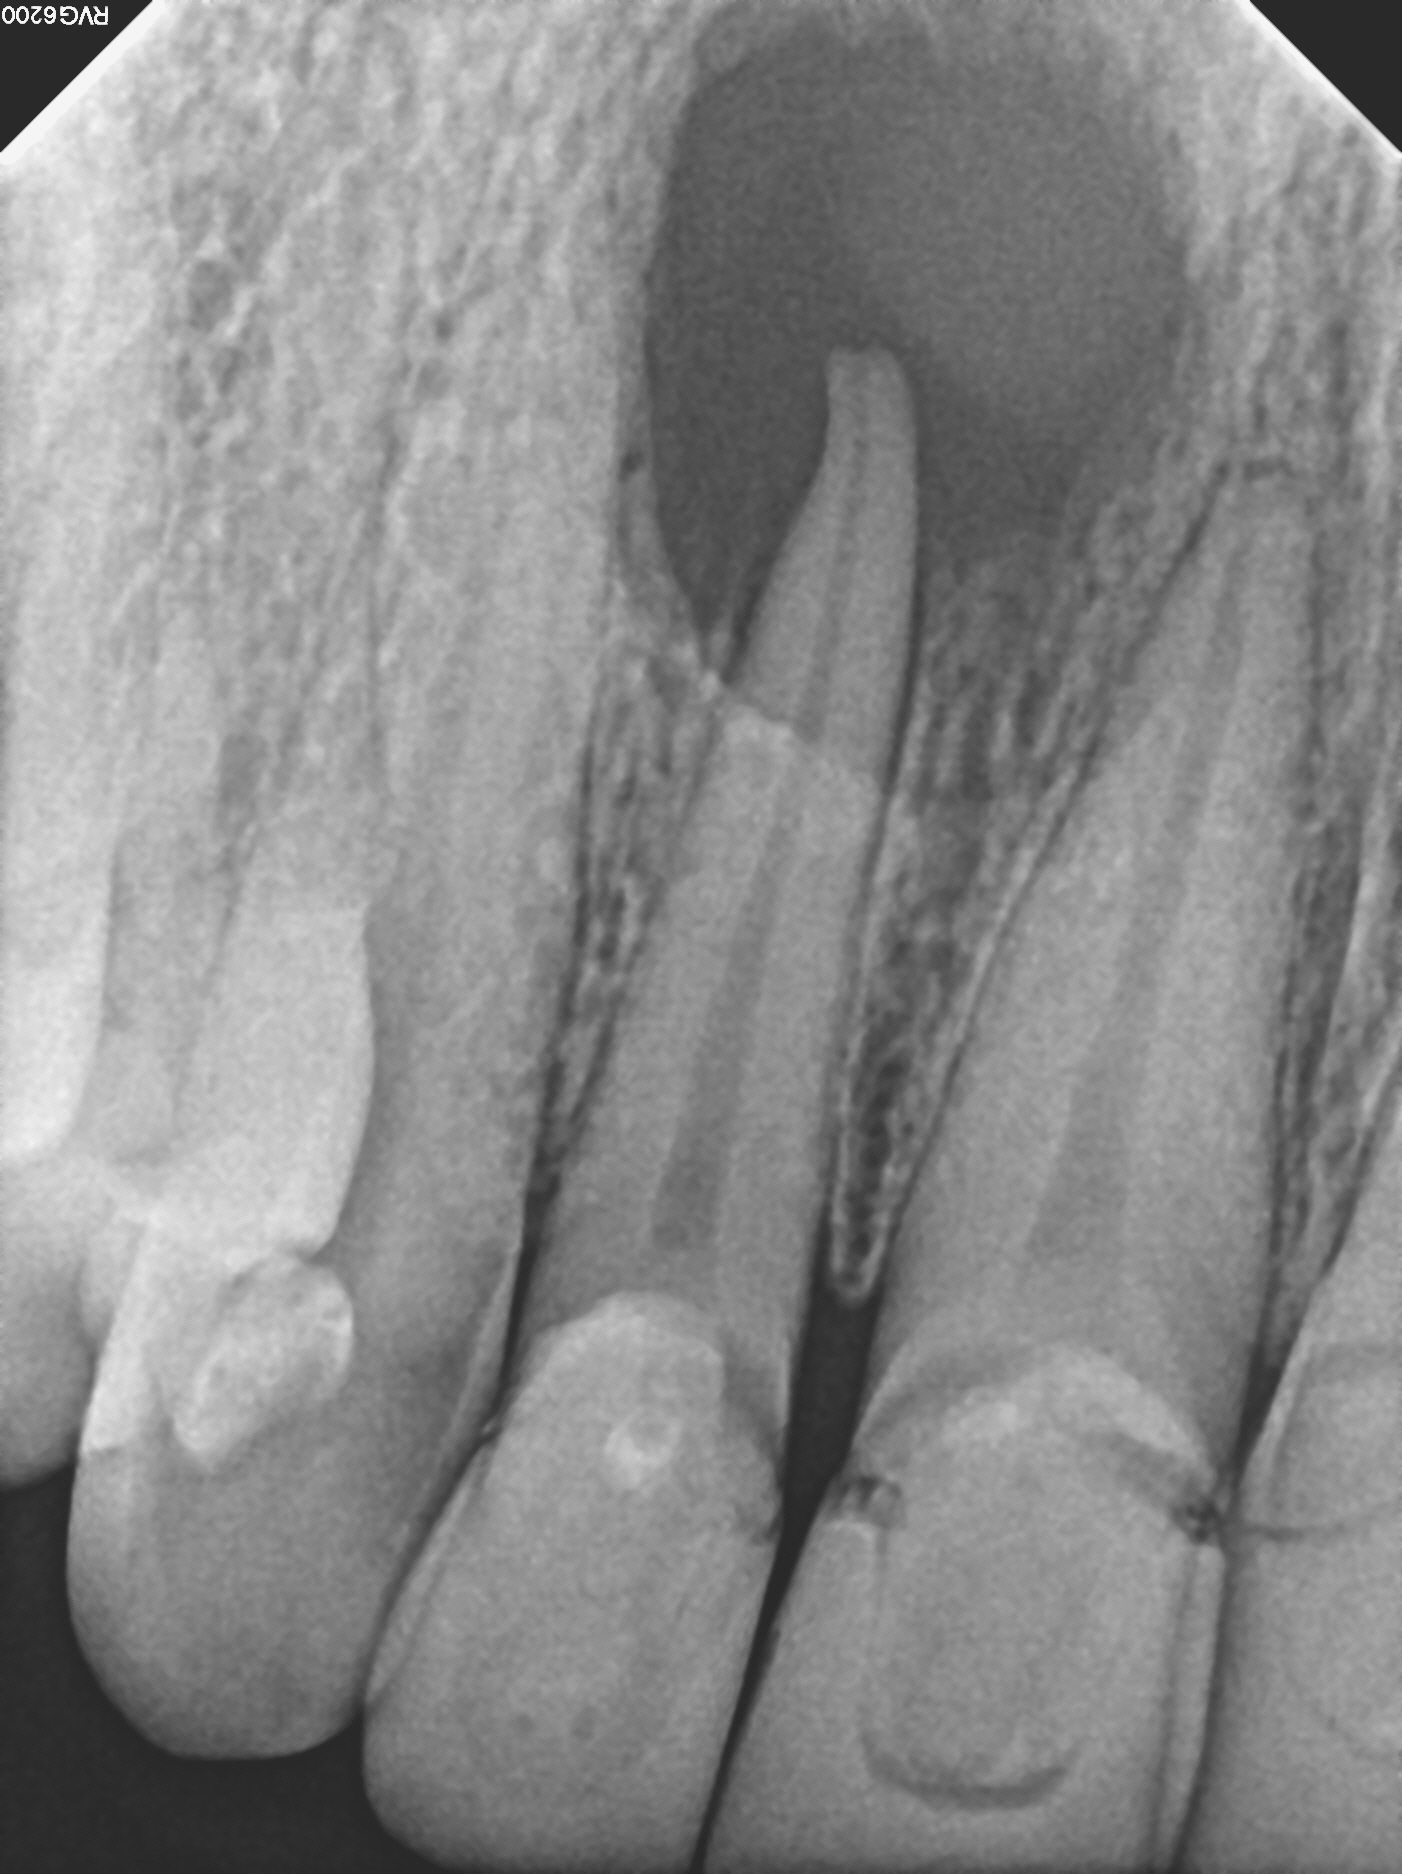

1_pre1

3_post1

Case 9

This case shows just how curved the roots of teeth can be, which can lead to the nerve canal spaces being difficult to fully treat. These types of cases are often referred to endodontic specialists for treatment due to the added complexity of the curved roots.